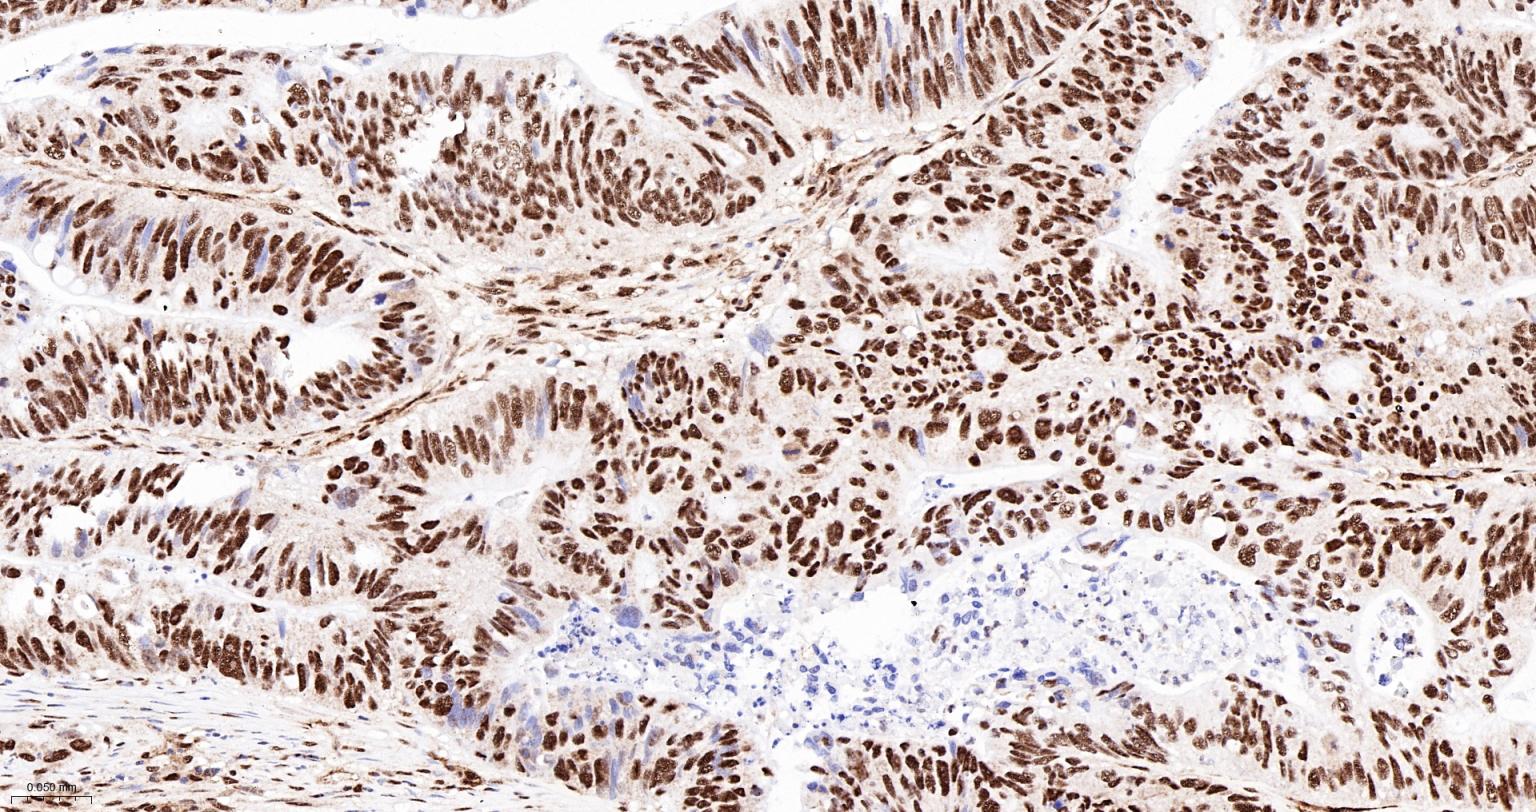

Paraformaldehyde-fixed, paraffin embedded Human Stomach; Antigen retrieval by boiling in sodium citrate buffer (pH6.0) for 15 min; The section was incubated with PRPF19 Monoclonal Antibody, Unconjugated (bsm-61268R) at 1:200 overnight at 4°C, followed by conjugation to the bs-0295G-HRP and DAB (C-0010) staining.